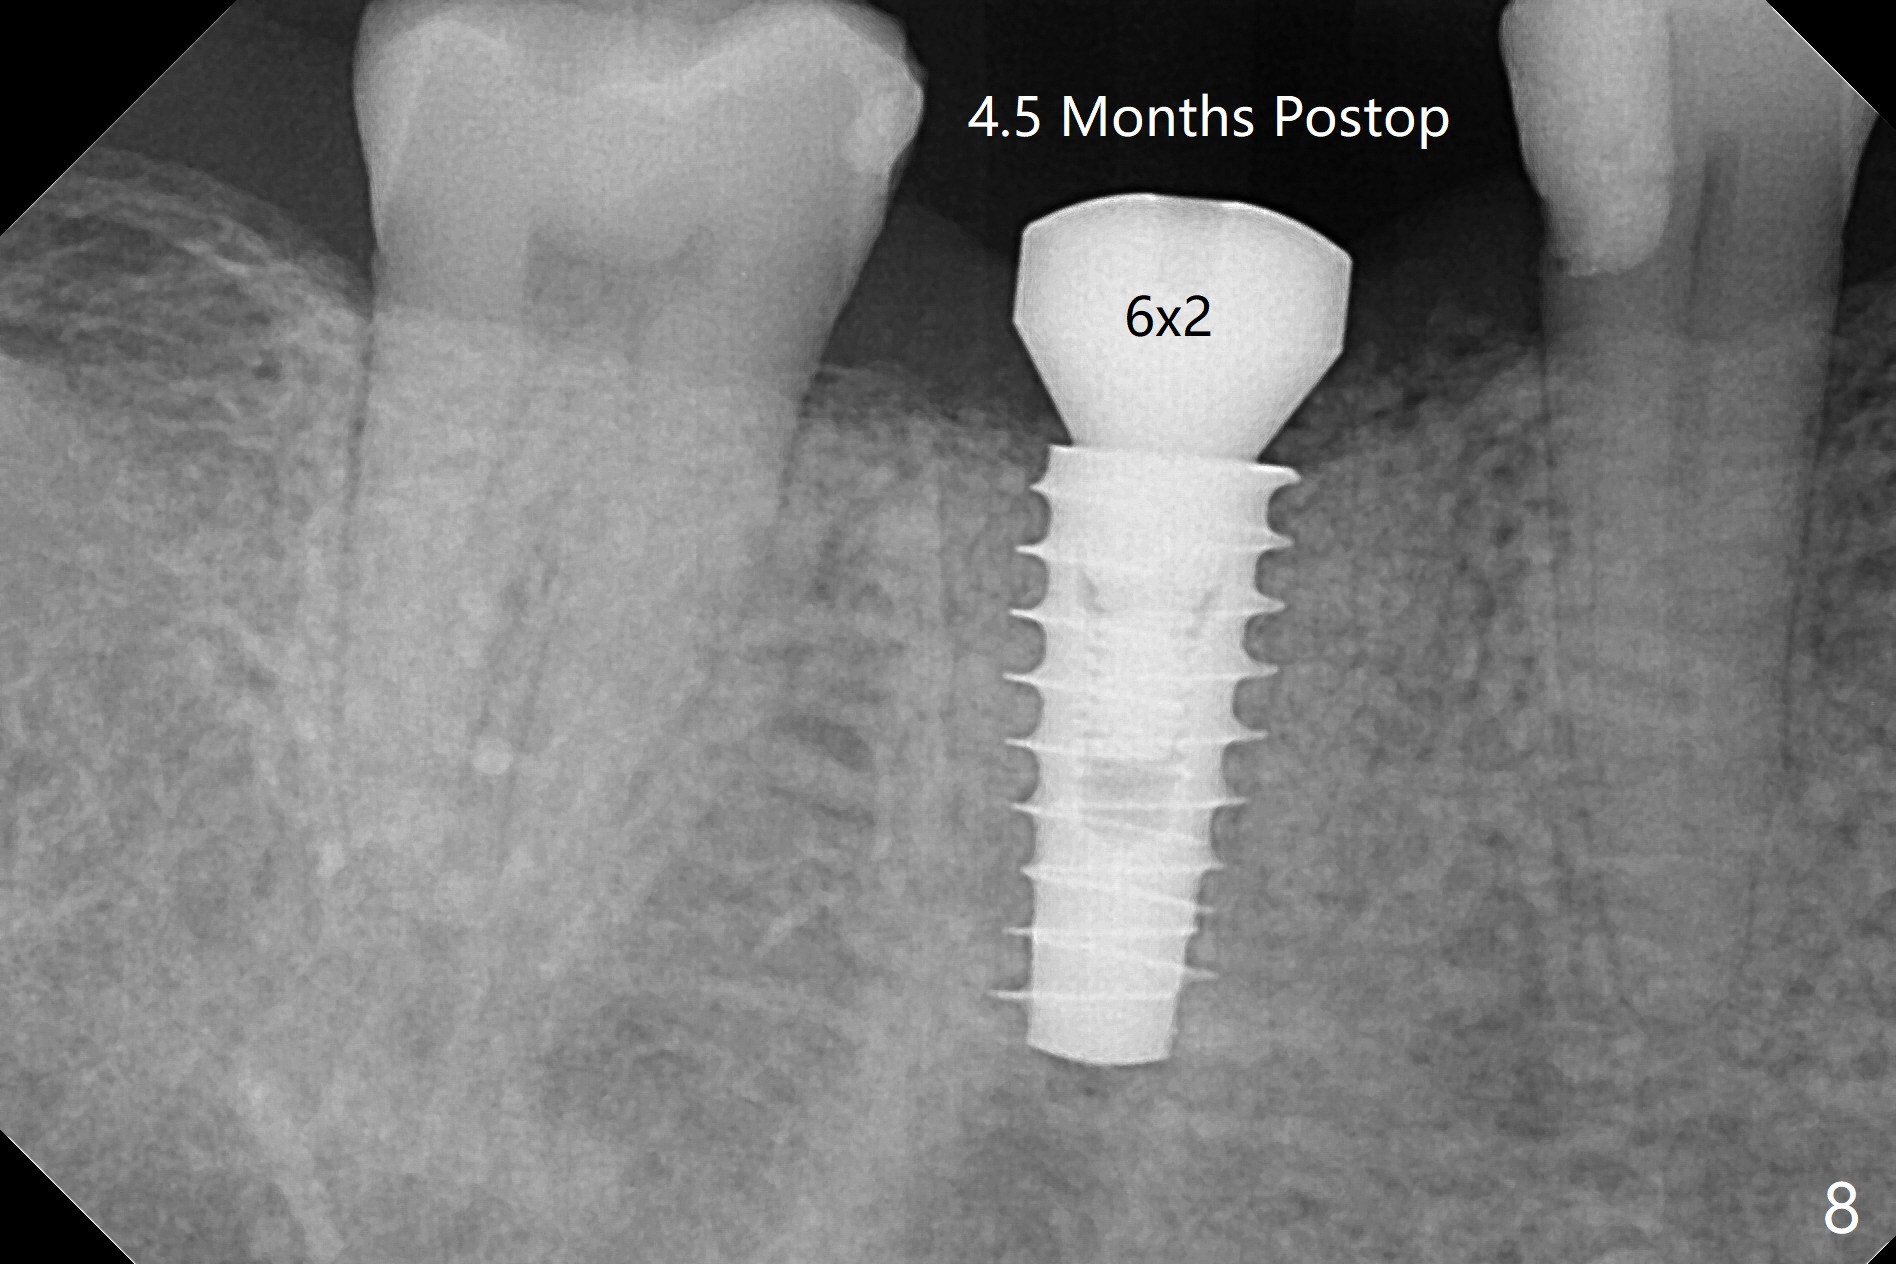

牙冠断裂,好像容易保留牙根,其实还挺多工作。使用12毫米平磨钻头后,中隔中央形成凹陷,不过使用2.2x7.3毫米钻头后,钻洞开始偏移远中(图一)。完成3.5x11.5毫米钻洞,4x10毫米报废植体扭力很高(图二)。为了植入5x11毫米植体(扭力35Ncm),必须使用4.5x11.5毫米钻头(图三)。虽然根尖骨质不多,稳定性部分来自残余颊侧,舌侧中隔。即刻放置的基台远中舌侧必须大量磨去(图四:^)才有足够空间做临时牙冠,说明牙冠会折裂病人咬合力大。保留牙根工作量大,仍有偏差(与图五(设计)相比),仿佛好处不大,以后少做。由于临时牙冠舌侧做的大些,术后八天取出修正,伤口愈合正常(图六)。术后一个月一部分骨粉好像被转化为牙龈(图七)。术后3.5月病人抱怨咀嚼疼痛,植体松动,放置愈合基台。一个月后植体仍松动,疼痛(图八)。术后6.5月,植体不再松动,放置修复基台(图九),取模。